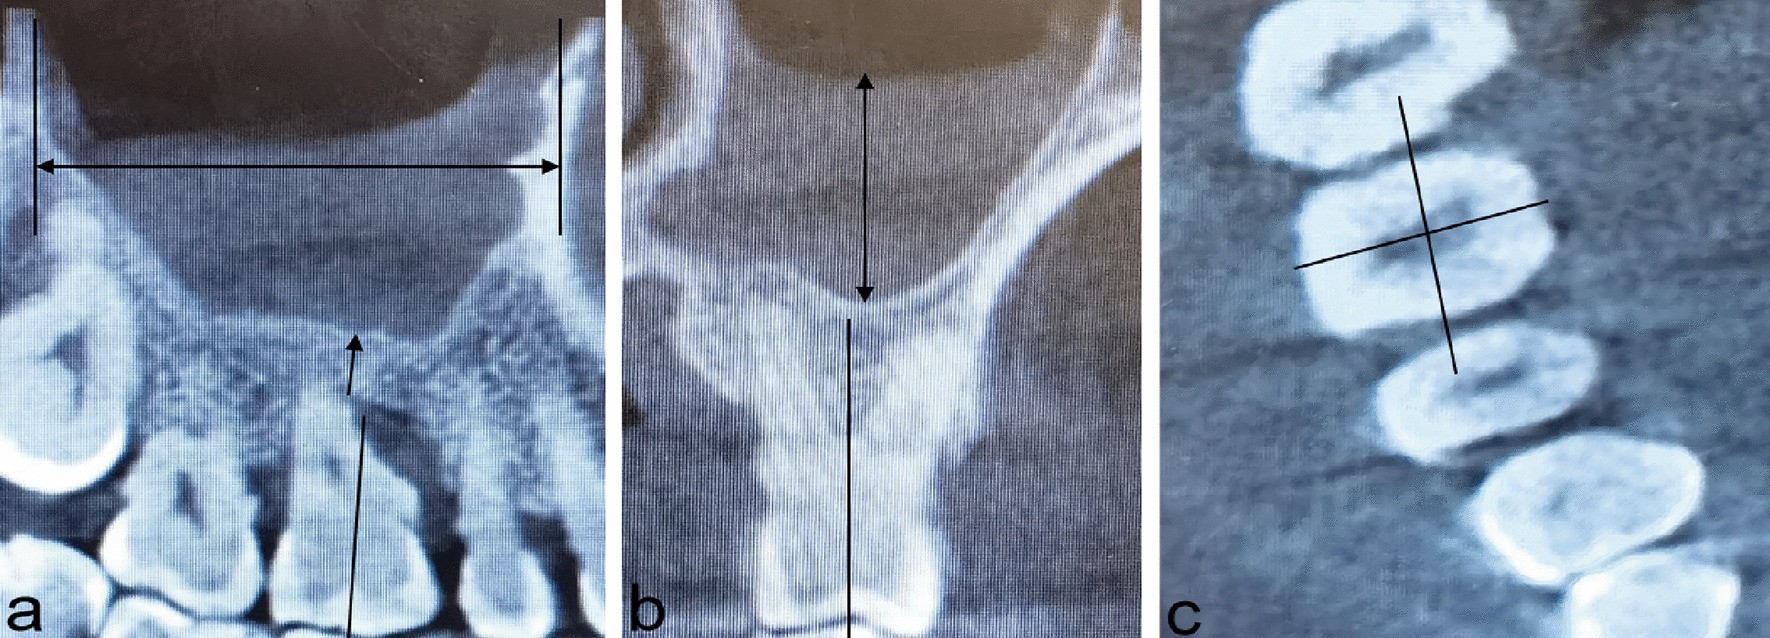

Fig. 1

Three-dimensional reconstruction image of maxMT. a Sagittal view, double-ended arrow: the length of maxMT; Single-ended arrow: the minRABH. b Coronal view, double-ended arrow: the thickness of the mucosa of the maxillary sinus. c Horizontal view. Abbreviations: maxMT maxillary sinus mucosal thickening; miniRABH minimum residual alveolar bone height.